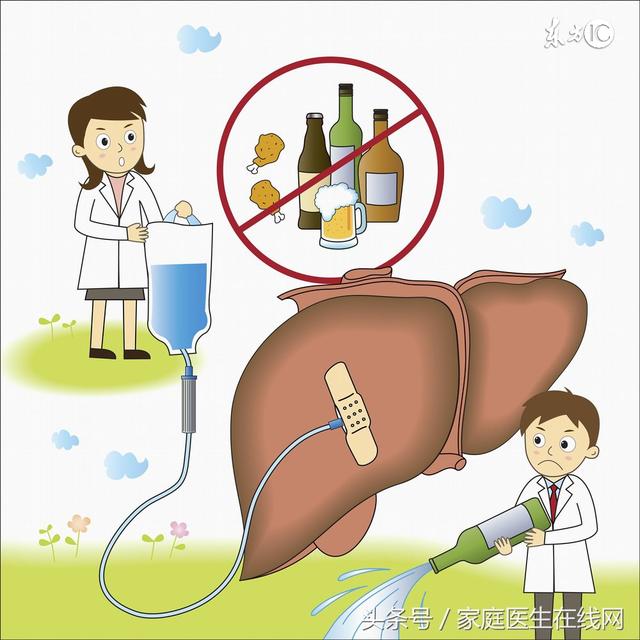

肝臟是最容易生病的器官

由於肝臟最忙最累,又由於肝臟面對有毒有害物質的侵襲,再由於肝髒又任勞任怨,所以肝臟最容易受到傷害,患病最多,也最難治,諸如,甲肝、乙肝、丙肝、黃疸型等等,酒精肝、脂肪肝、肝硬化等等。了解了肝臟的特點,我們就能應該善待和保護自己的肝臟。從醫藥學研究和臨床時間來看,目前大多數肝病是很難單純依靠藥物來治好的。能夠有效激活人體的免疫系統,調節肝臟代謝,清除體內毒素,幫助受損的肝細胞修復,有利於肝細胞生成。

吸煙酗酒。煙中含有的尼古丁,以及煙霧中的上千種有害物質都會損害肝臟等臟器,是導致疾病、誘發癌症的主要危險因素之一。酒的代謝產物乙醇對肝臟來說極其不利,酗酒會增加脂肪肝、酒精肝的風險。

愛吃油膩。肝臟是脂肪運輸的樞紐。消化吸收後的一部分脂肪進入肝臟,以後再轉變為體脂貯存起來。飢餓時,貯存的體脂可先被運送到肝臟,然後進行分解。吃太多油膩食品,容易導致脂肪代謝紊亂,使脂肪堆積於肝臟內形成脂肪肝。

保護肝臟日常飲食注意事項

1、多喝水:多喝水可補充體液,增強血液循環,促進新陳代謝,多喝水還可促進腺體,尤其是消化腺和胰液、膽汁的分泌,以利消化、吸收和廢物的排除,減少代謝產物和毒素對肝臟的損害。

3、喝酒前吃點東西:喝酒秘方少不了喝酒前吃東西。少喝酒自然少傷害,如果一定要喝,並且想做點預防措施,那就是盡量多吃些食物墊墊肚子,食物下肚後可以在胃黏膜、腸黏膜上形成一層保護膜,不但保護腸胃,也能阻礙部分酒精進入血液,降低醉酒程度。